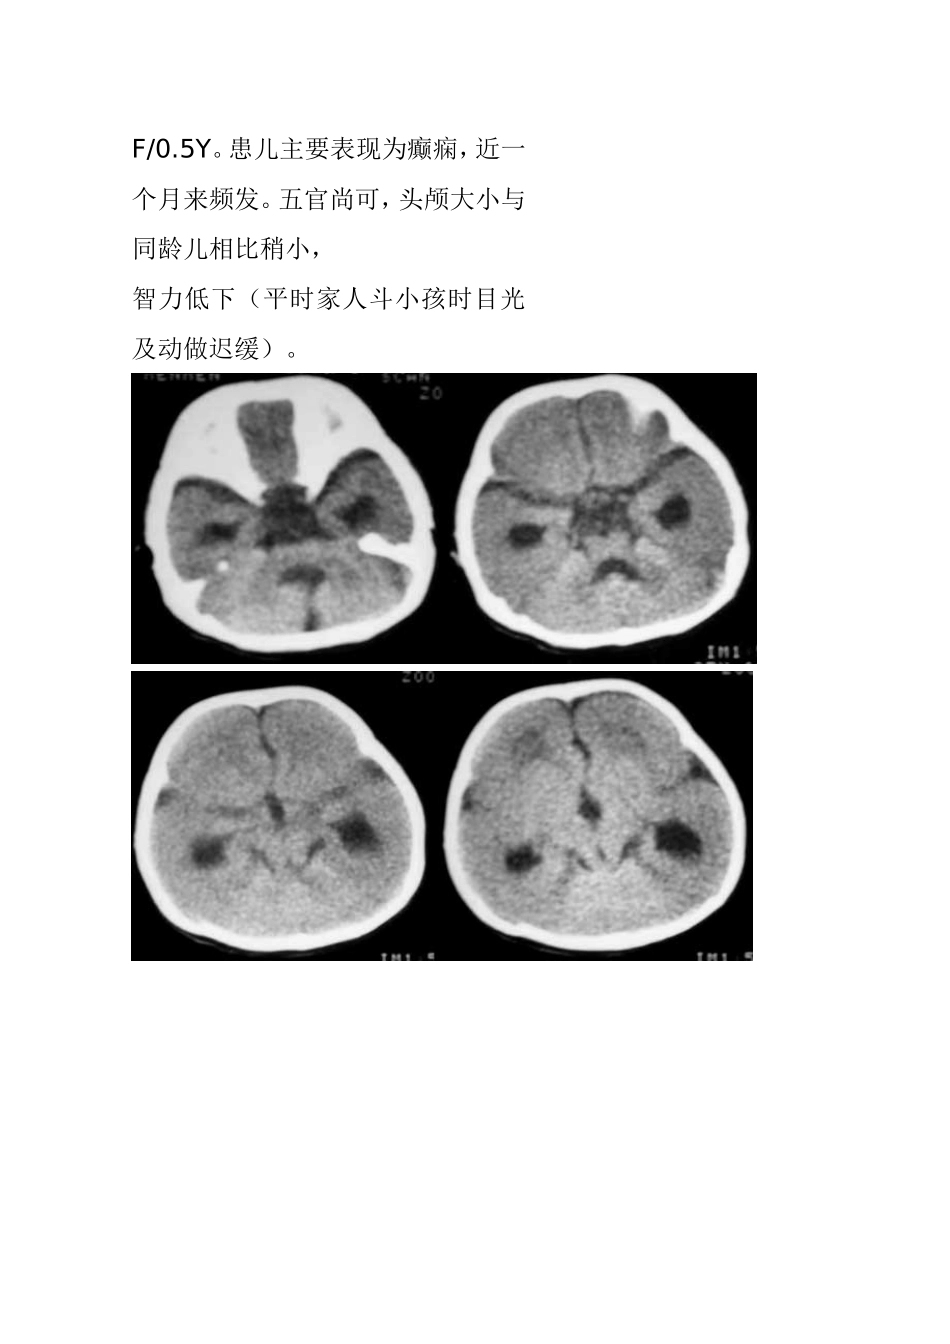

F/0.5Y。患儿主要表现为癫痫,近一个月来频发。五官尚可,头颅大小与同龄儿相比稍小,智力低下(平时家人斗小孩时目光及动做迟缓)。结果:无脑回畸形伴胼胝体发育不良男,8个月,间歇性惊厥3个月。患儿体检无明显异常发现,心肺正常。血常规正常。今日临床以脑炎?要求CT检查。平扫显示大脑半球皮质明显增厚,脑白质减少,两侧额顶脑沟少而浅,呈现巨大脑回表现,部分大脑皮质缺乏沟回,影像:巨脑回畸形。女性,22岁,左侧上下肢瘫痪21年结果:巨脑回畸形[病理]无脑回畸形和/或巨脑回畸形:无脑回畸形指大脑表面光滑,无脑回结构;巨脑回畸形指大脑停留在先天性巨脑回原始阶段,脑回宽、扁。两者仅为畸形成度不同,可同时存在于脑的不同部位。前者多在顶枕部,后者多位于额部。镜下管前者大脑皮质结构异常,皮质分层不完全或不分层,常见不成熟的神经细胞。后者皮层保留了原始皮层的4曾神经细胞结构,神经细胞分化不成熟。白质中常发现异位的神经细胞,有时呈结节状。[临床表现]无脑回畸形患儿在新生儿期常有小头畸形和轻微面部异常,以后表现出智力落后。完全性无脑回畸形者大多在2岁前死亡。巨脑回存活者常有智力低下和癫痫。[CT表现]无脑回畸形和/或巨脑回畸形,前者主要表现为脑表面光滑,脑回、脑沟消失,皮层增厚,白质减少。后者主要表现为侧裂变浅、增宽,脑回增宽,皮质增后,内表面光滑,白质减少,患侧脑室系统扩大。此外,无脑回畸形两侧裂变浅,呈“8”字形表现。[本例CT平扫]显示双侧大脑半球皮层明显增厚、表面光滑、无脑回及脑沟,皮层下白质稀少。双侧外侧裂变浅、凹陷,整个双侧大脑半球呈“8”字形表现,脑室系统扩大。前纵裂增宽、增深,与第三脑室向连通。双侧侧脑室扩大、分离。